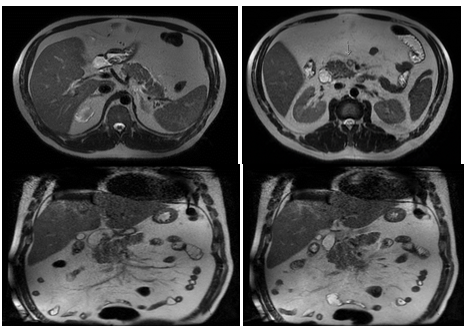

Figure 2 Fatty liver, Gallbladder with dilated wall without gallstones, no bile duct dilation nor stones. Inflammatory peripancreatic fat changes due to pancreatitis. No peripancreatic collections, increased SMV diameter with flow defect indicating thrombosis.

Figure 3 Periappendicular free fluid with dilated appendicular lumen, with a small 17x16mm collection. Inflammatory changes in the periduodenal mesenteric fat, peripancreatic and mesogastric zones with SMV opacification and flow defect.